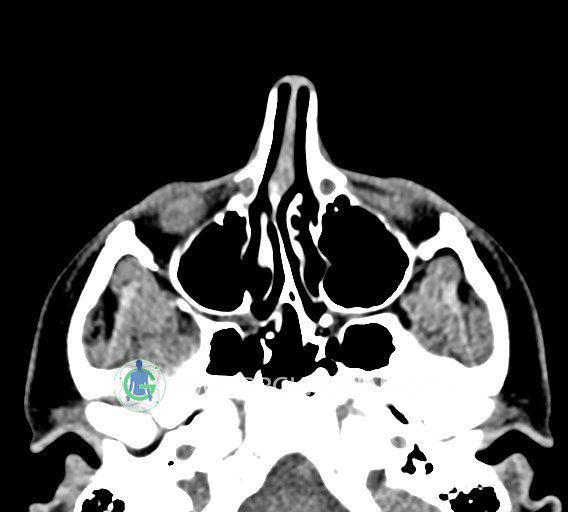

سی تی اسکن سینوس ها یک روش تصویربرداری است که با استفاده از تشعات ایکس تصاویری با جزییات از ناحیه خالی داخل صورت (سینوس ها) ایجاد میکند. در این کیس استئوم فرعی سینوس در دیواره سینوس ماگزیلاری، انحراف سپتوم و کونکا بولوزا مشاهده می شود.

در HRCT اسپيرال از سينوس هاي پارانازال مقاطع کرونال و آگزيال ( 16 اسلايس و مقاطع ظريف 1.5 mm بدون فاصله ، با پنجره استخواني و نسج نرم ) :

– انحراف سپتوم مياني بينی به راست

– کونکا بولوزا در کونکای ميانی چپ و

– اوستيوم فرعي در ديواره مديال سينوس ماگزيلاري راست

مشهود است .